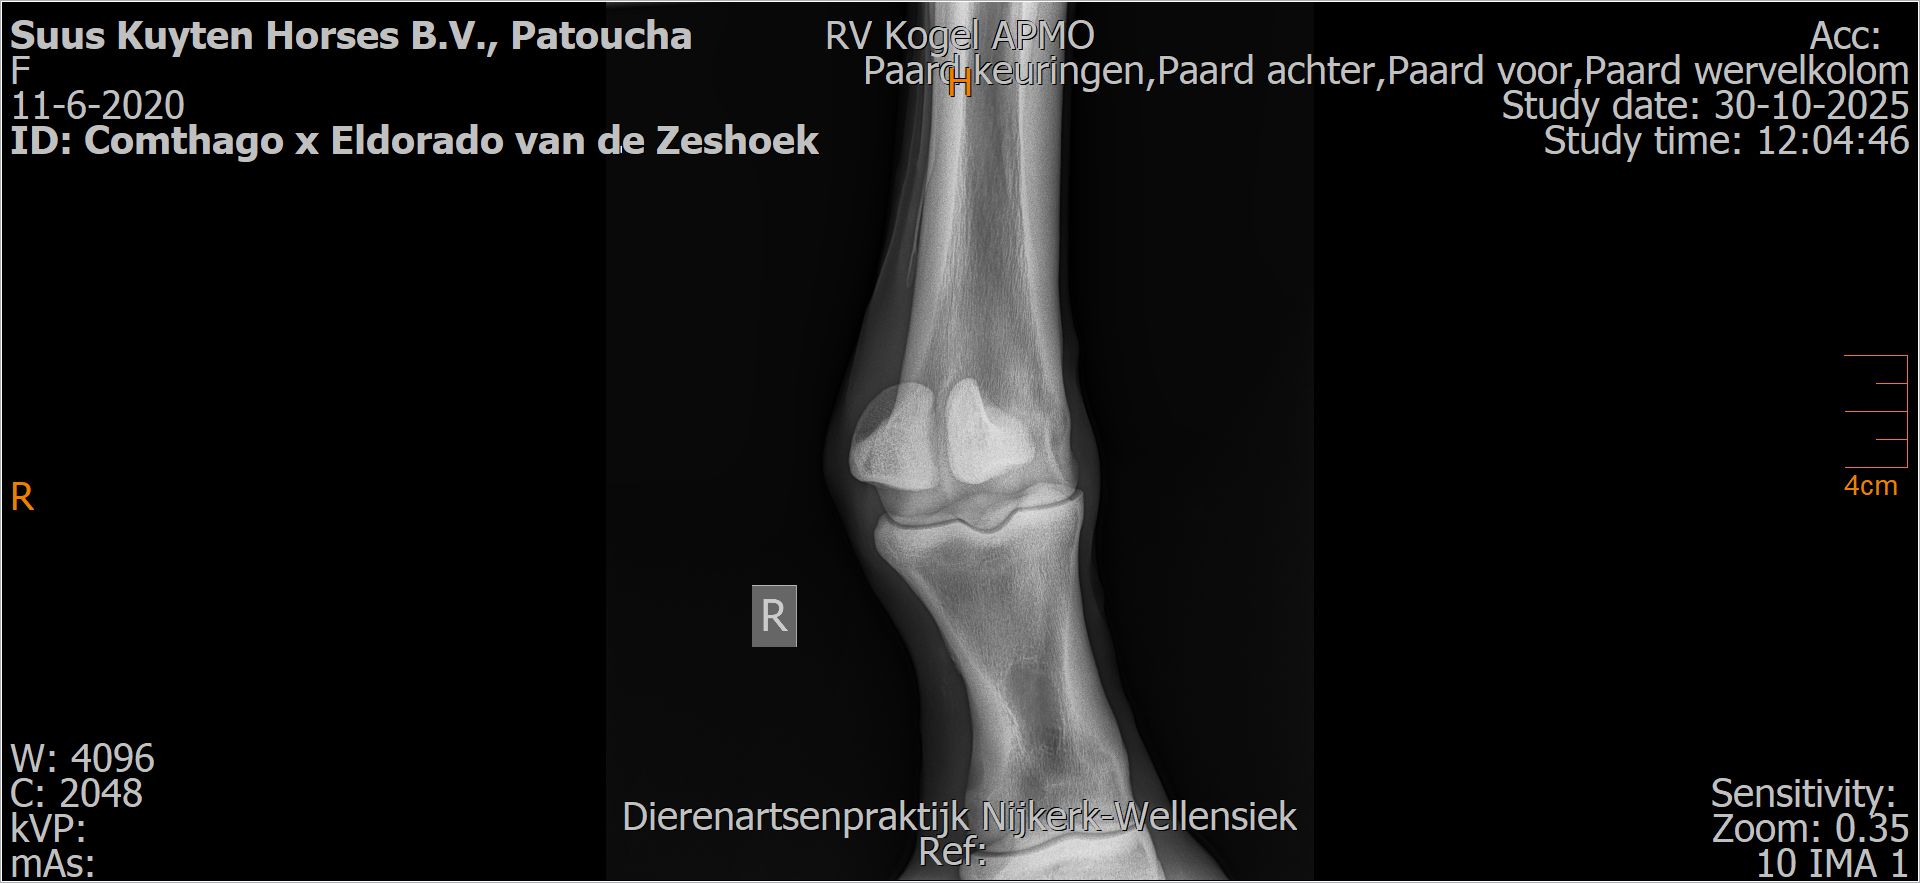

Patoucha

Leeftijd:

7

Röntgenfoto’s